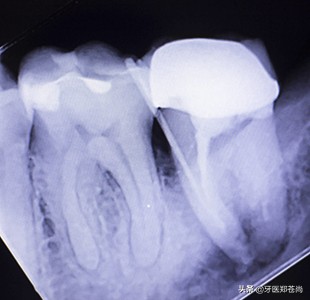

根管治疗后的牙齿

根管治疗后的牙齿,内部疼痛得以缓解,整颗患牙保留了下来,但是因为失去了牙神经,内部内清空,失去了输送营养的“通道”,所以整颗牙会变脆弱,需要做个牙冠,或者是使用其它修复体,将其修复保护起来,方可正常使用。